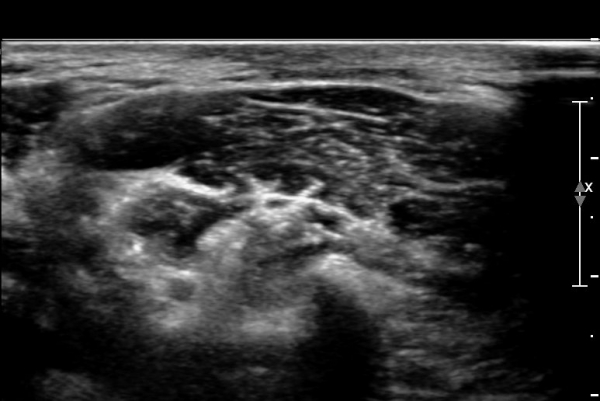

ÃÊÀ½ÆÄ ¼Ò°ß : ¸ñ ¿ÜÃø Á߾ӺΠȾ´Ü¸é°Ë»ç»ó Èä¼âÀ¯µ¹±Ù ÈÄ¹Ý °ß°©°Å±Ù Ç¥Ãþ¿¡¼­ ôÃߺνŰæÀÌ Àú¿¡ÄÚ

¿øÇü ±¸Á¶¹°·Î °üÂûµÈ´Ù(»çÁø 1, 2, 3).

ŽÃÊÀÚ¸¦ ¾à°£ ¸»´ÜÀ¸·Î À̵¿ÇÏ´Ï ¼ö¼ú ¹ÝÈçÀÌ °üÂûµÇ°í  ¼ö¼ú¹ÝÈç ÈÄ¹æ ½ÉºÎ¿¡¼­

ôÃߺνŰæÀÌ °üÂûµÇ´Âµ¥ ½Å°æÀÇ ¿¬¼Ó¼ºÀº À¯ÁöµÇ¾î ÀÖ´Ù(»çÁø 4, 5).